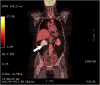

Leiomyosarcomas of the uterine cervix are rare, mostly occurring in perimenopausal women. Diagnosis is based on pathology and immunohistochemistry. Surgery with a total abdominal hysterectomy and bilateral salpingo-oophorectomy remains the standard. A female patient in her 60s presented with heavy postmenopausal bleeding. Vaginal ultrasound scan and magnetic resonance imaging showed a large strongly vascularized cervical mass with features suspicious of sarcomatous degeneration. Positron Emission Tomography-Computed Tomography (PET-CT) did not reveal any evidence of metastases nor lymphadenopathy, but presence of right hydronephrosis. An abdominal hysterectomy with bilateral salpingo-oophorectomy, and end-to-end anastomosis of the right ureter, was performed. Pathology showed an International Federation of Gynecology and Obstetrics (FIGO)-stage 1B leiomyosarcoma of the uterine cervix. No adjuvant treatment was given. Adjuvant radiotherapy reduces the risk of recurrence but no survival impact. The benefit of adjuvant chemotherapy is questionable given the lack of randomized trials. Multidisciplinary research concerning molecular alterations of the disease is required to determine optimal management strategies with potential novel molecular therapies.